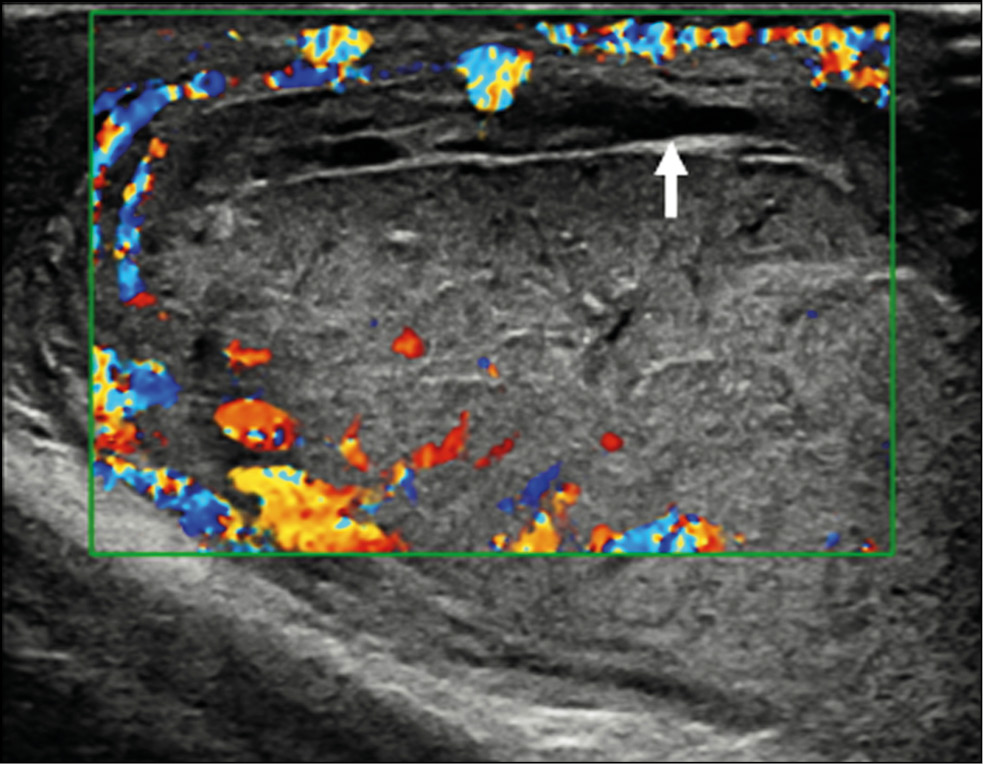

Imaging, particularly ultrasonography, plays a crucial role in the assessment of scrotal trauma and directs patient management toward conservative or surgical treatment. Conventional B-mode and color Doppler ultrasonography are the main imaging techniques in the evaluation of the testicle in trauma but may underestimate the extent of injury. The most important information for the surgeon is the integrity or interruption of the tunica albuginea and the extent of vital testicular tissue. The latter is often difficult to assess with conventional ultrasonography because the injured testicle is often hypovascular even in vital regions due to testicular edema that compromises vascular flow. The selective use of advanced techniques such as contrast-enhanced ultrasonography is important in identifying testicular viability when color Doppler ultrasonography is equivocal.